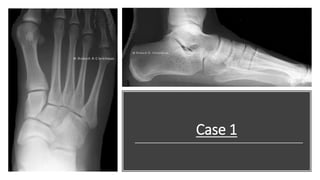

Lateral view

This is a lateral view of the right foot. I see a decrease in

calcaneal inclination angle and 1st metatarsal declination

angles. The talar declination angle and Kite’s angle is

increased. Increase in Meary’s angle with long axis of

talus pointing plantar-ward. The cyma line is "broken"

anteriorly.

Diagnosis: Pes Planus.

This is DP view of the right foot. Accessory

navicular type 3 noted. The is an increase in

talocalcaneal and cuboid abduction angles; The

forefoot adduction angle is decreased.

Talonavicular joint "congruency" is less than

75%.